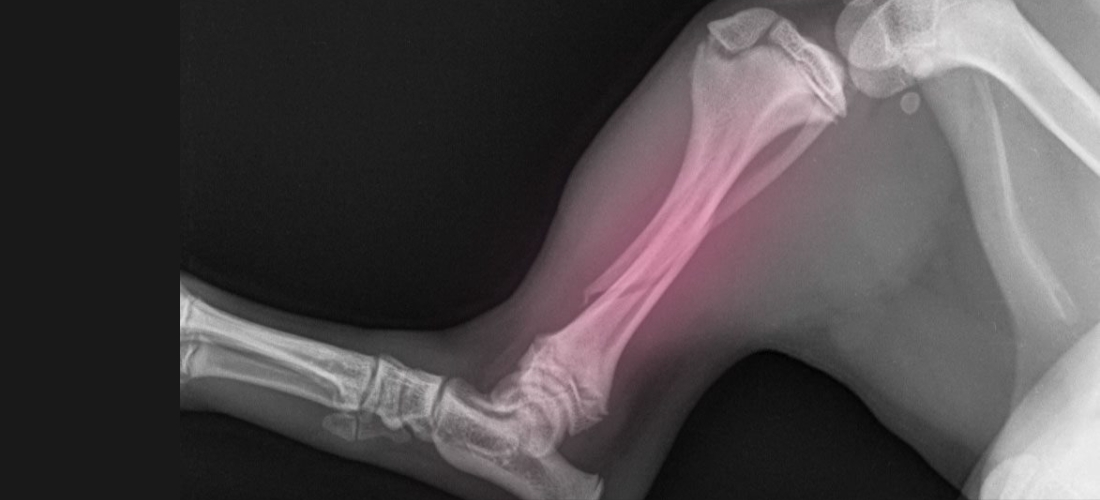

PDSA vet said: “Despite the pain killers, Cooper was still painful. We took an X-ray under sedation which showed a spiral fracture of the tibia (the main large bone in a dog’s lower leg between the knee and ankle). Luckily the bones were stable so the fracture had a very good chance of healing without surgery, using painkillers, strict rest and a special bandage called a Robert Jones bandage, a bulky dressing that supports the leg and keeps the bones in place while they heal.